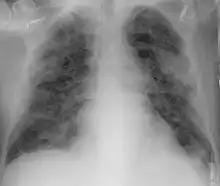

Imaging

Chest CT scans may be helpful to diagnose COVID‑19 in individuals with a high clinical suspicion of infection but are not recommended for routine screening.[174][186] Bilateral multilobar ground-glass opacities with a peripheral, asymmetric, and posterior distribution are common in early infection.[174][187] Subpleural dominance, crazy paving (lobular septal thickening with variable alveolar filling), and consolidation may appear as the disease progresses.[174][188] Characteristic imaging features on chest radiographs and computed tomography (CT) of people who are symptomatic include asymmetric peripheral ground-glass opacities without pleural effusions.[189]

Many groups have created COVID‑19 datasets that include imagery such as the Italian Radiological Society which has compiled an international online database of imaging findings for confirmed cases.[190] Due to overlap with other infections such as adenovirus, imaging without confirmation by rRT-PCR is of limited specificity in identifying COVID‑19.[189] A large study in China compared chest CT results to PCR and demonstrated that though imaging is less specific for the infection, it is faster and more sensitive.[173]